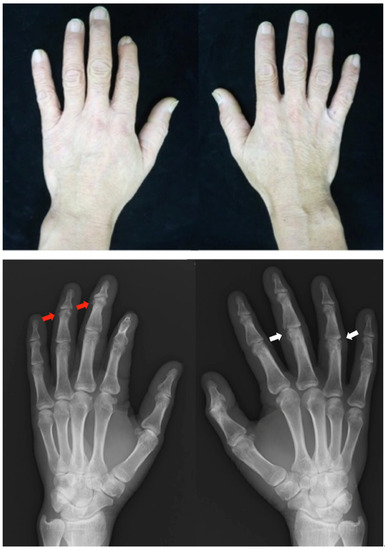

2.1. Case 1

Patient: Man in his 70s

2.2. Case 2

Patient: Man in his 60s